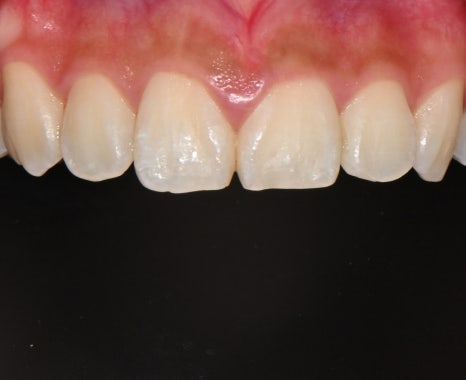

📸 After

– 밝고 매끄러운 치아 톤

– 균형 잡힌 앞니 라인

– 미소선과 조화되는 자연스러운 조형

환자분은 “치아가 예뻐졌다기보단, 내 얼굴이 환해진 느낌”이라며

처음으로 사진 찍을 때 입을 활짝 열어 웃게 됐다고 전해주셨습니다.